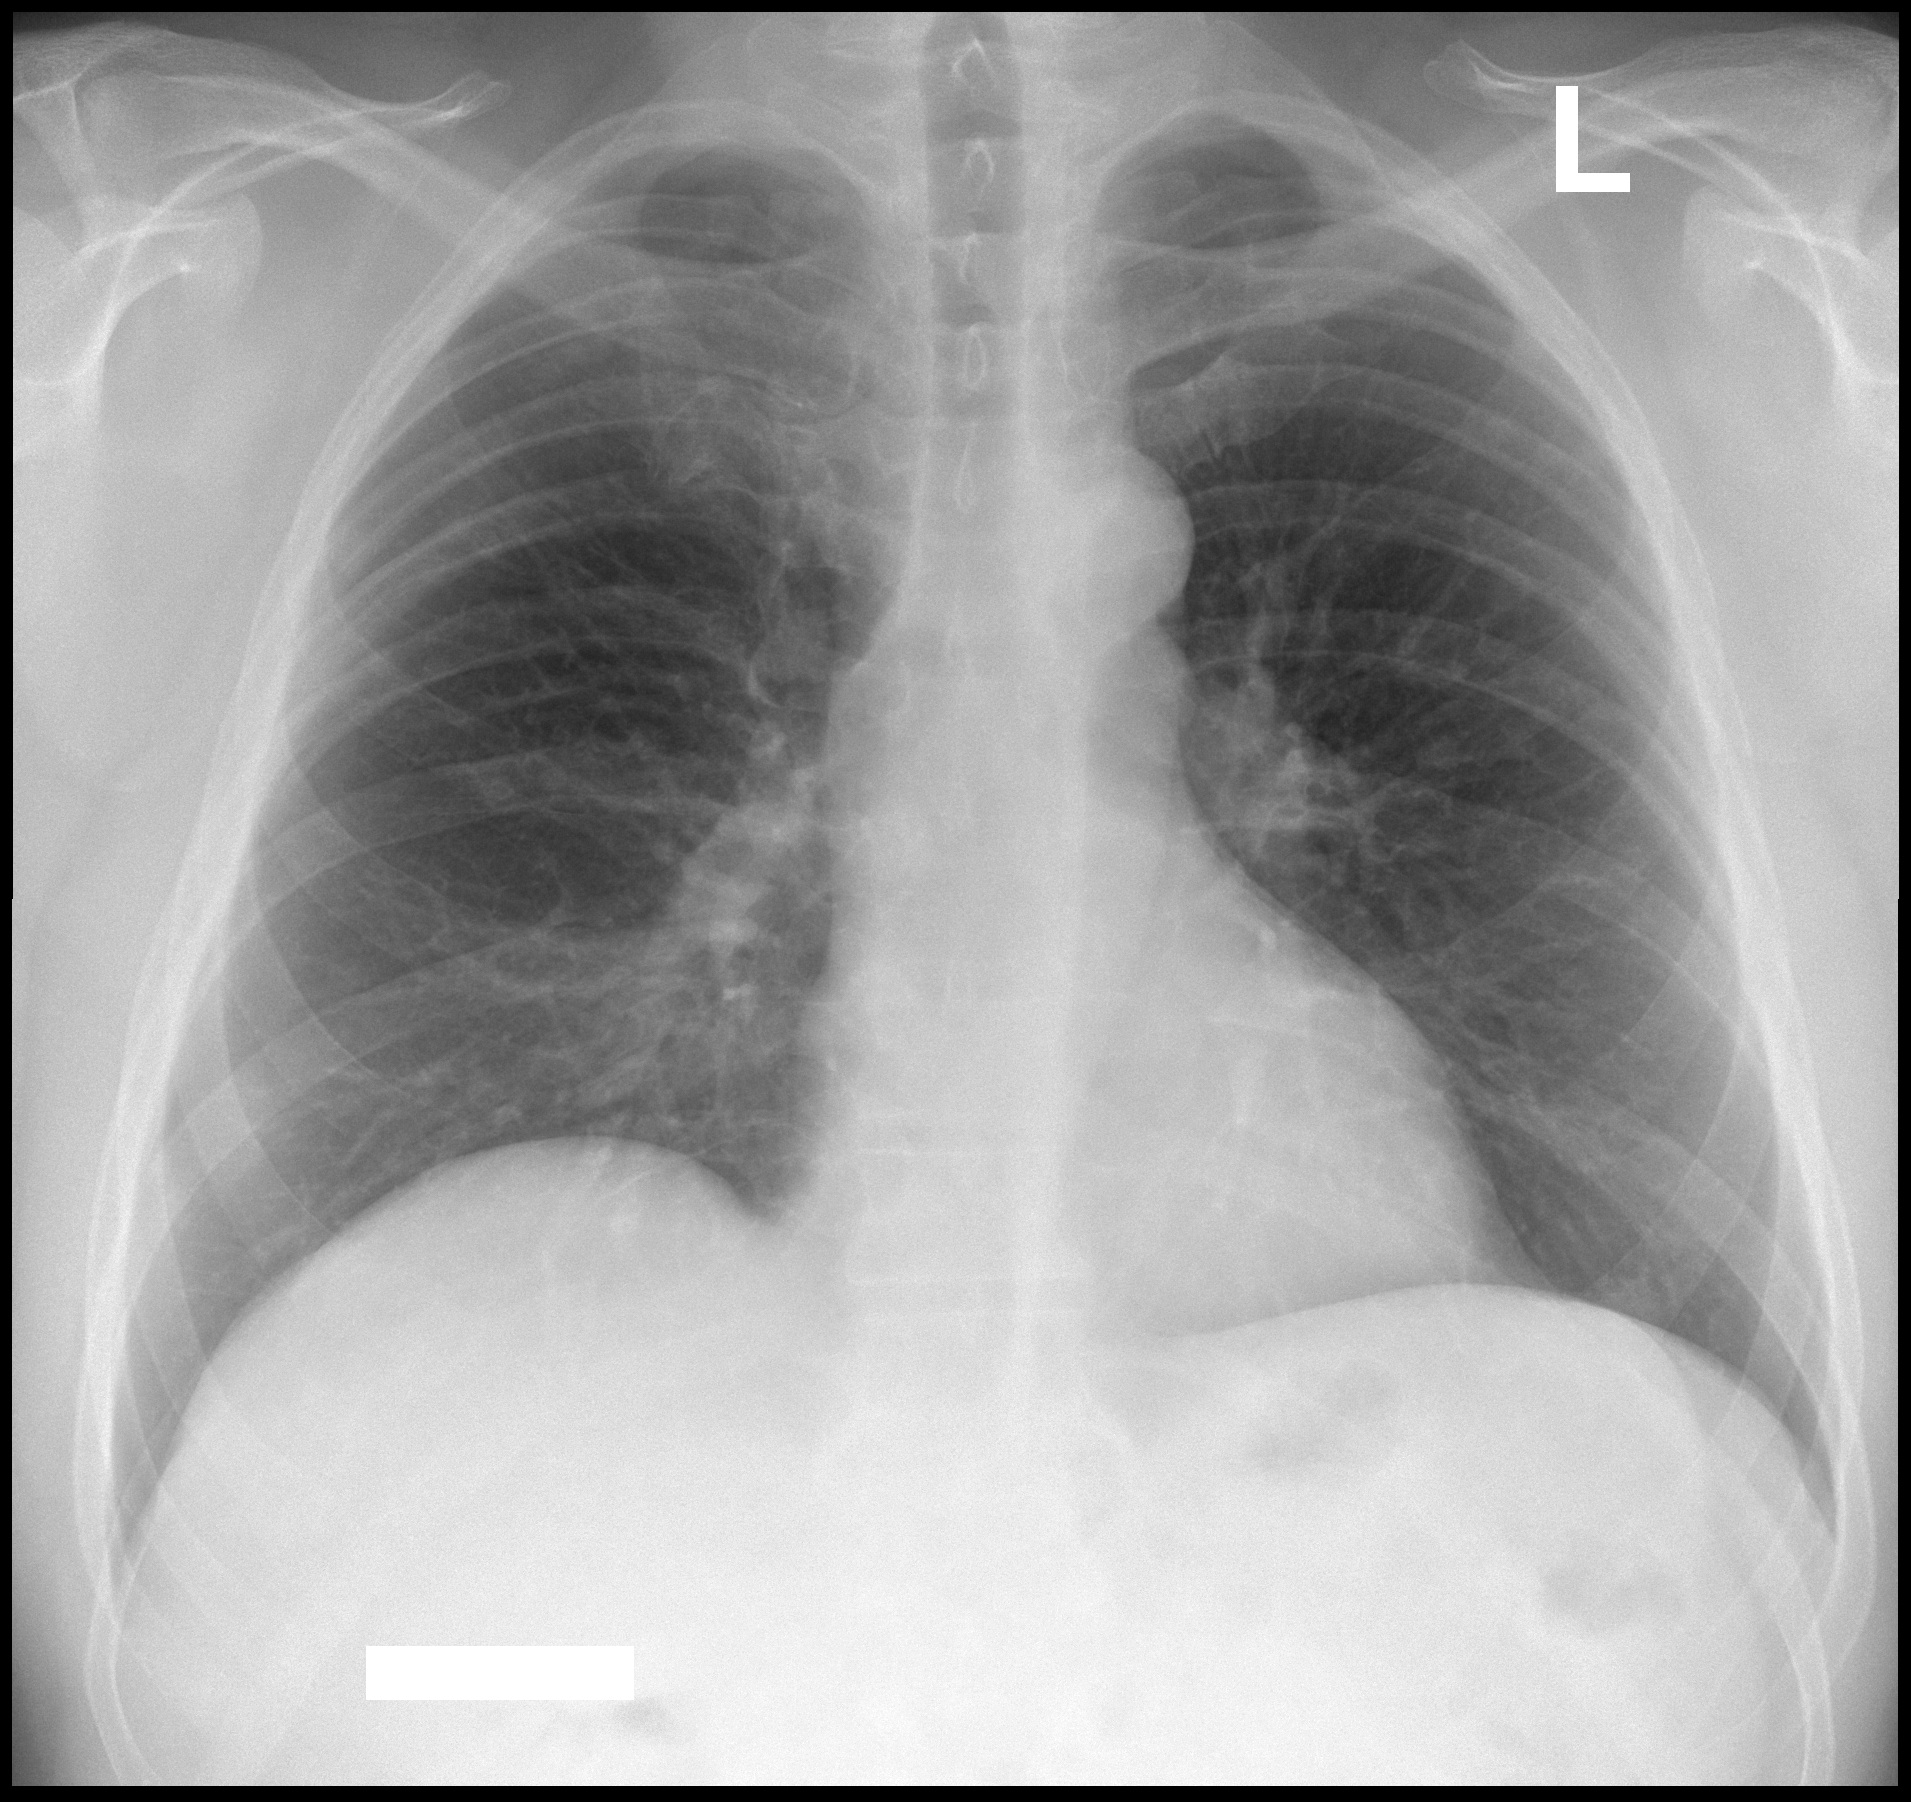

Нормальная рентгенограмма легких: что нужно знать

Раздел: Мудрость в объективе